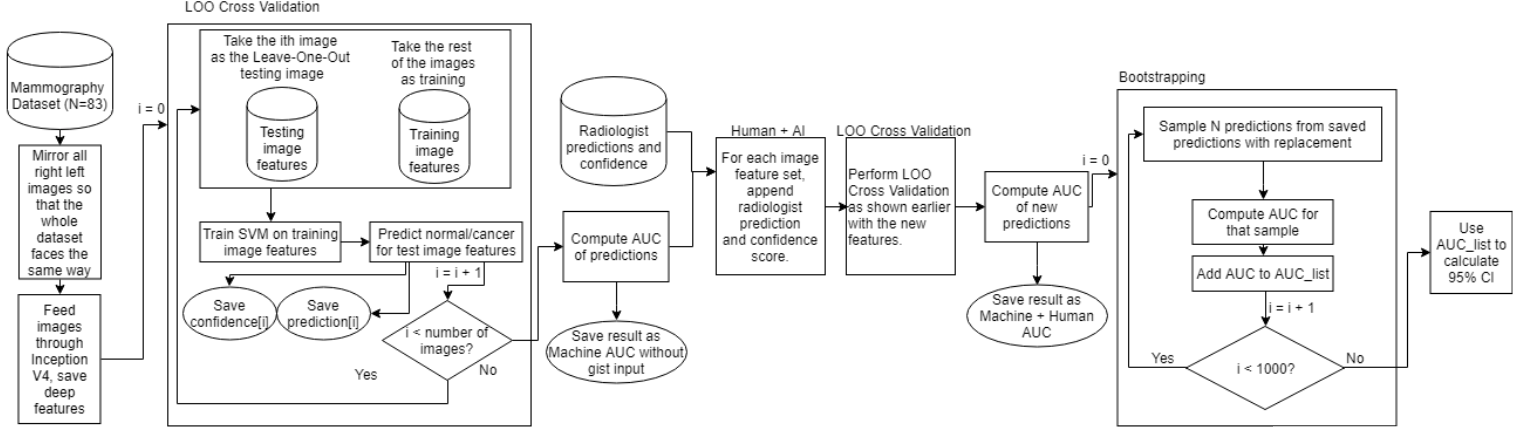

We use a transfer learning approach to combine radiologist gist information with features from a CNN classifier to investigate the benefits of coupling the machine and human expertise (Figure 1). Our method begins with the preprocessing of input dataset of mammogram images with four methods: (1) no changes, (2) horizontally flip all left breast images, (3) crop muscle fibers out of each image, (4) combine (2) and (3), i.e., crop muscle fibers out and then horizontally flip all left breast images. When we horizontally flip left breast images, our resulting dataset will have images that face the same direction. Next, we feed each dataset into established CNNs Inception-v4 and VGG-19, pretrained on ImageNet, a corpus of over 14 million non-medical images [8]. Though these networks are meant to classify non-medical objects. we use deep features to provide an abstract representation from within the network to classify mammograms. Usually these features are unintelligible to humans, but some describe intuitive aspects of an image, such as edges, spirals, or gradients. In each network, we take all values from neurons of one layer near the final classification layer to obtain our feature vector. Finally, we perform classification based on the feature vector obtained from the CNN using LightGBM (LGBM) [9] and a linear support vector machine (SVM). Putting together, we have 4 processing steps of muscle cropping and rotation, two CNNs for deep features, and two classifiers for final classification, giving us end-to-end systems.

We test these 16 systems with and without appending the radiologist gist responses to the end of the feature vector before classification. Original radiologists scores for detecting breast cancer were in range [0,100]. Radiologists’ input is set to 0 (normal) if the average response is greater than 50 and to 1 (malignant) otherwise. We also calculate a “confidence score” from the radiologist gist input for each image: .

Transfer learning method. Figure 3 illustrates the transfer learning method we use. To generate deep features for the input images, we test two deep CNNs, VGG19 and Inception-v4. Both are pre-trained to classify over 1000 classes from the ImageNet corpus containing over 14 million non-medical images. We use the python package pretrained models to load both models. We take the values from nodes located in the first fully connected layer after the convolution layers to capture features about a full-field image fed through the network from Inception-v4, and use the values from the ReLu6 layer in VGG-19. Thus, we have 1536 features from Inception-v4 and 4096 features from VGG-19. This creates a feature vector which is used as input into a supervised learning algorithm. We test Microsoft’s LightGBM and a linear support vector machine (SVM) for binary classification as normal (0) or abnormal (1). LightGBM (LGBM) is a gradient-boosting framework using tree-based learning algorithms. We use the following parameters: learning rate = 0.003, boosting type = gbdt, objective = binary, metric = binarylogloss, subfeature = 0.5, numleaves = 10, mindata = 1, maxdepth = 1000. For the linear SVM, C=1000. Code is implemented in Python 3.6 with Keras and Tensorflow.

From the dataset, we use only the normal and malignant images for training and testing. Of these images, only those with radiologist responses are kept, leaving 83 images. This includes 42 abnormal mammograms and 41 normal. After the pre-processing step above, images were downscaled to pixels to fit the pre-trained Inception-v4 model properly via a function in pretrained models, or to fit the pre-trained VGG19 model. Image pixel values are normalized as they are when Inception-v4 and VGG-19 are trained. Leave-one-out (LOO) training and testing is used to generate 83 out-of-fold (OOF) predictions for each image in the set. Predictions will be 0 if classified as normal and 1 if classified as malignant. With our four pre-processing methods, two deep CNNs, and two classifiers, we have 16 models for classification that do not use radiologist gist response input.

The above process is repeated to create another 16 models that incorporate the radiologist gist input by appending the radiologist gist classification (0 or 1) and the calculated radiologist gist confidence (0.0-1.0), each multiplied by 100. This creates a new feature vector of length 1538 for each image when testing Inception-v4 feature vectors, and a feature vector length of 4098 when testing VGG19 feature vectors. We bootstrap 1000 AUC samples on the final predictions for each model to estimate the variance of the area under the receiver operating characteristic (AUC) for that model. A confidence interval is constructed using the middle of samples from the bootstrapping set to account for any skew in the samples. Cohen’s d is calculated using the mean difference divided by the standard deviation of the model. Significance between radiologist confidence subsets is tested using two-sample t-tests.